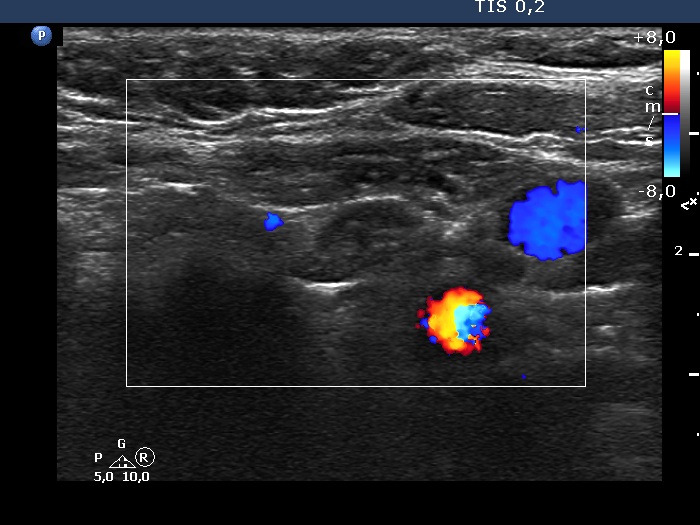

Right lobe, longitudinal scan

Lower pole and lower to the left lobe, longitudinal scan, color Doppler mode. The mass has no vascularity.